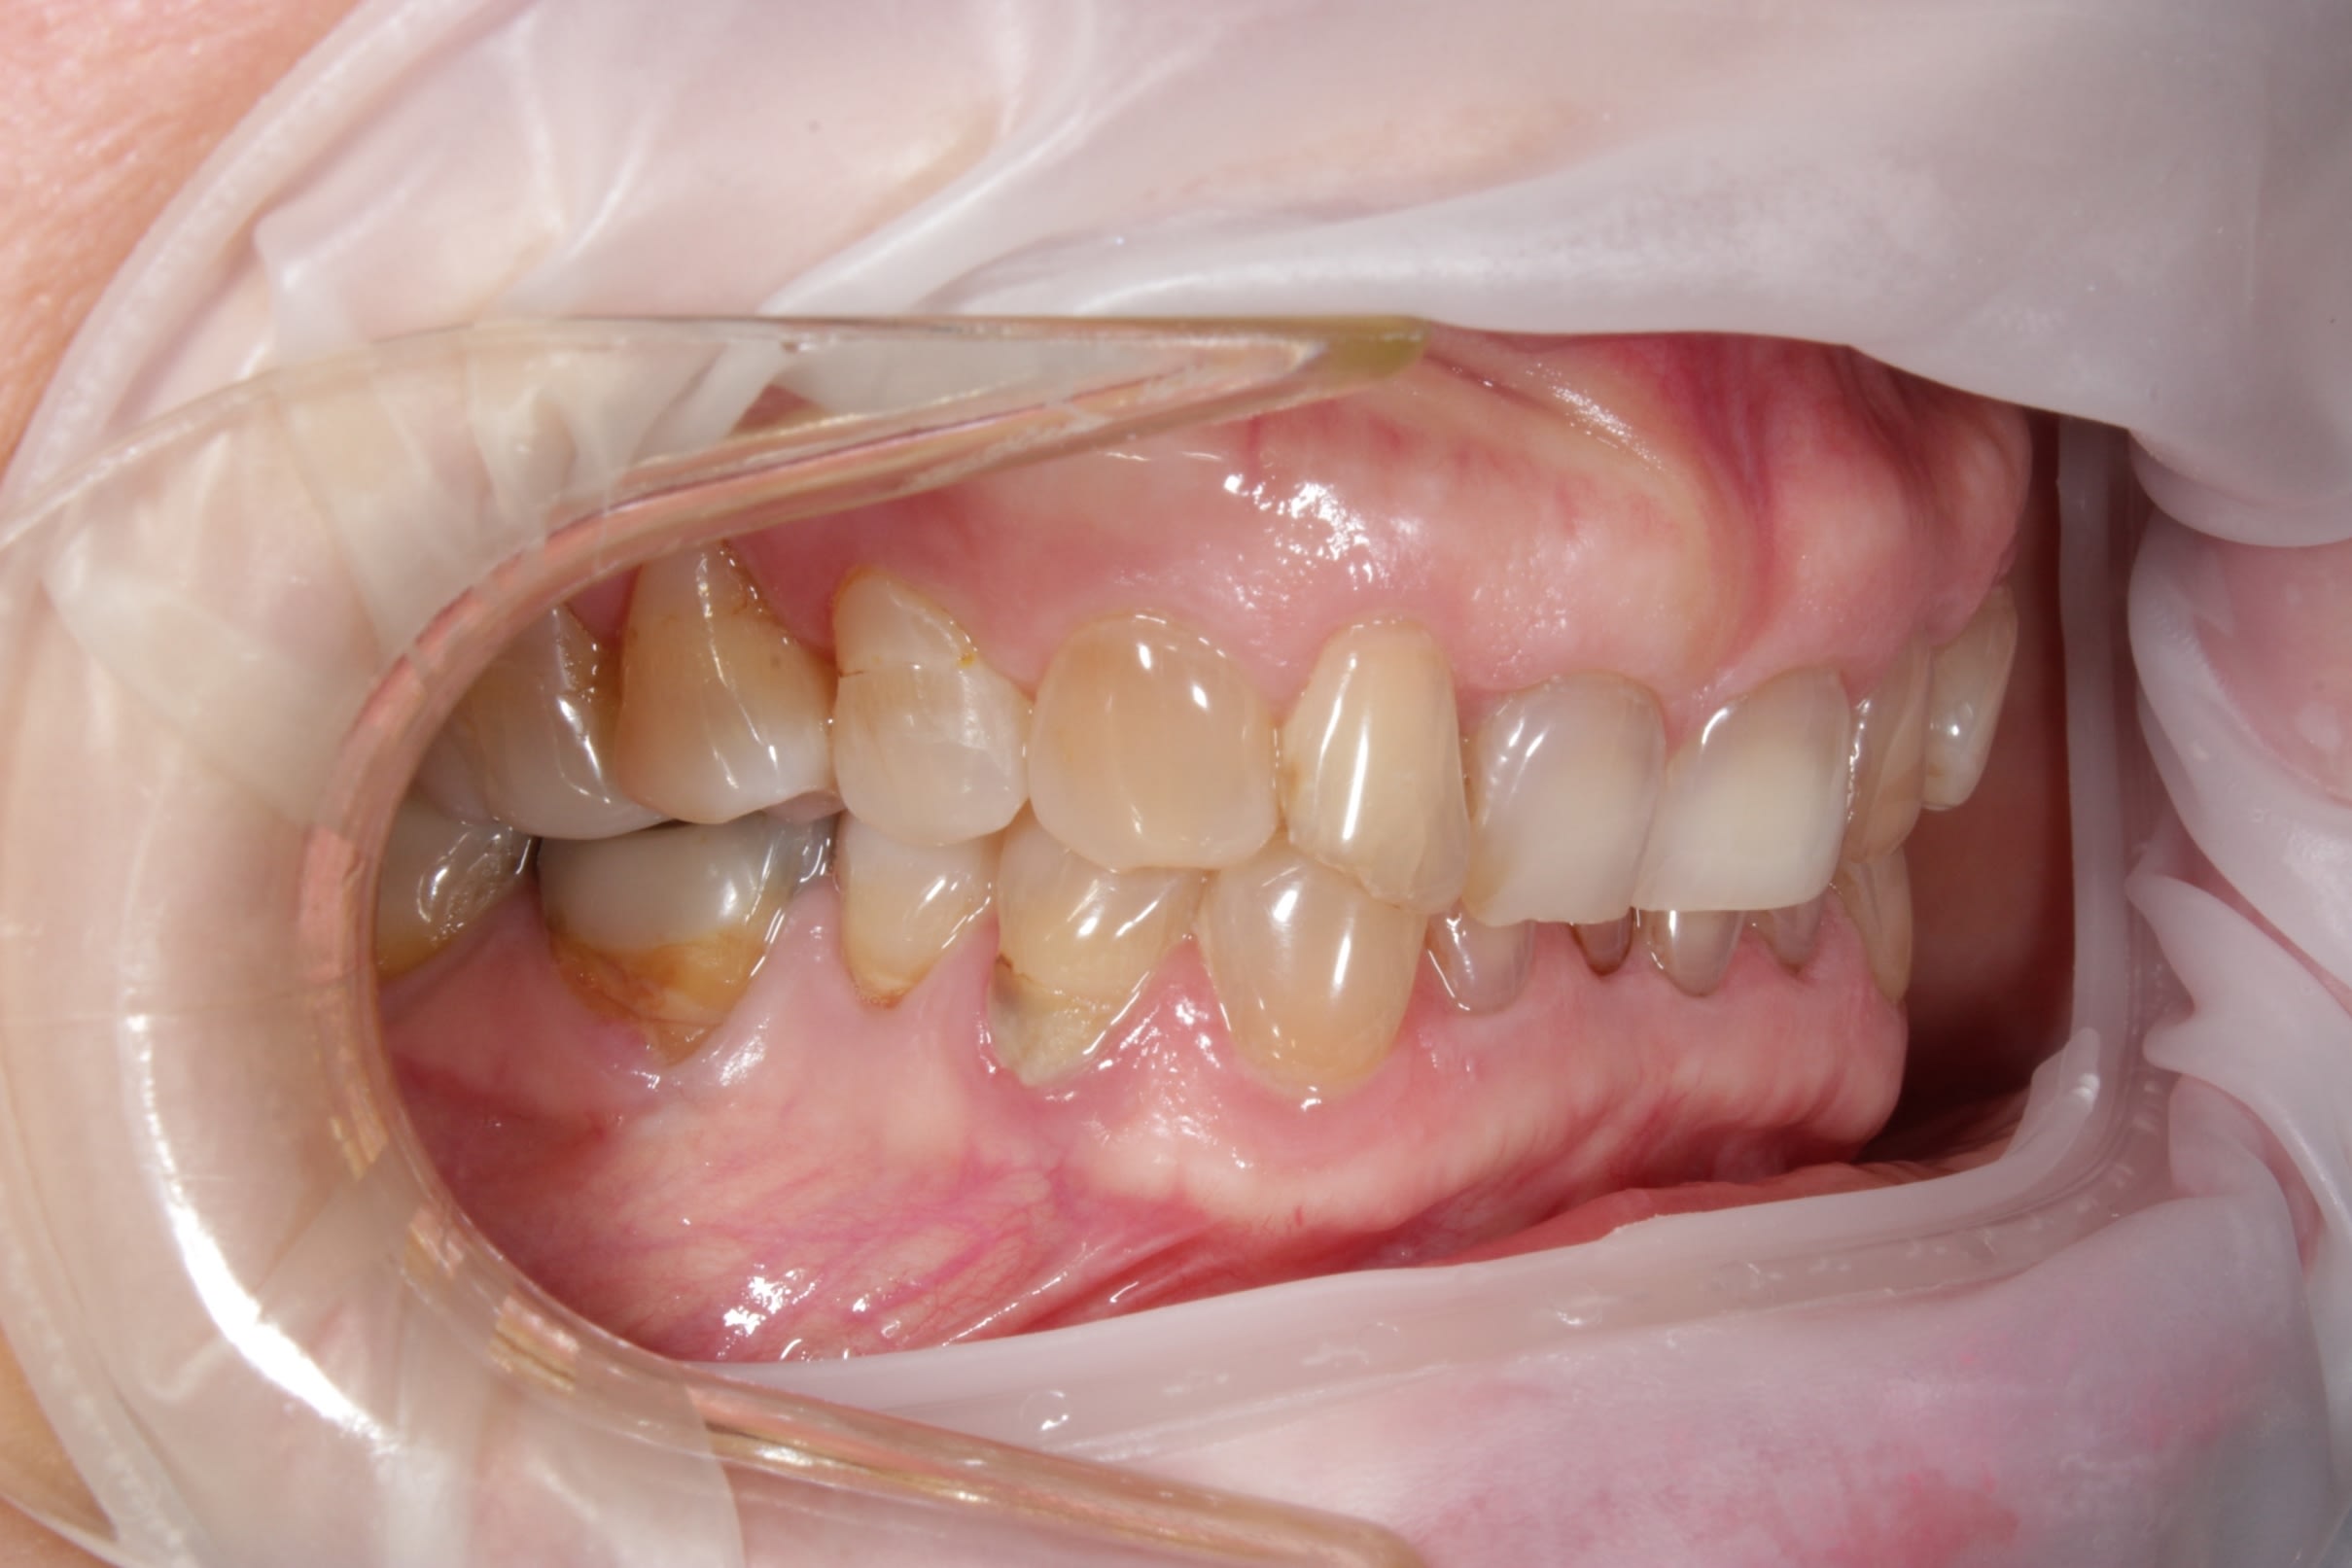

photos